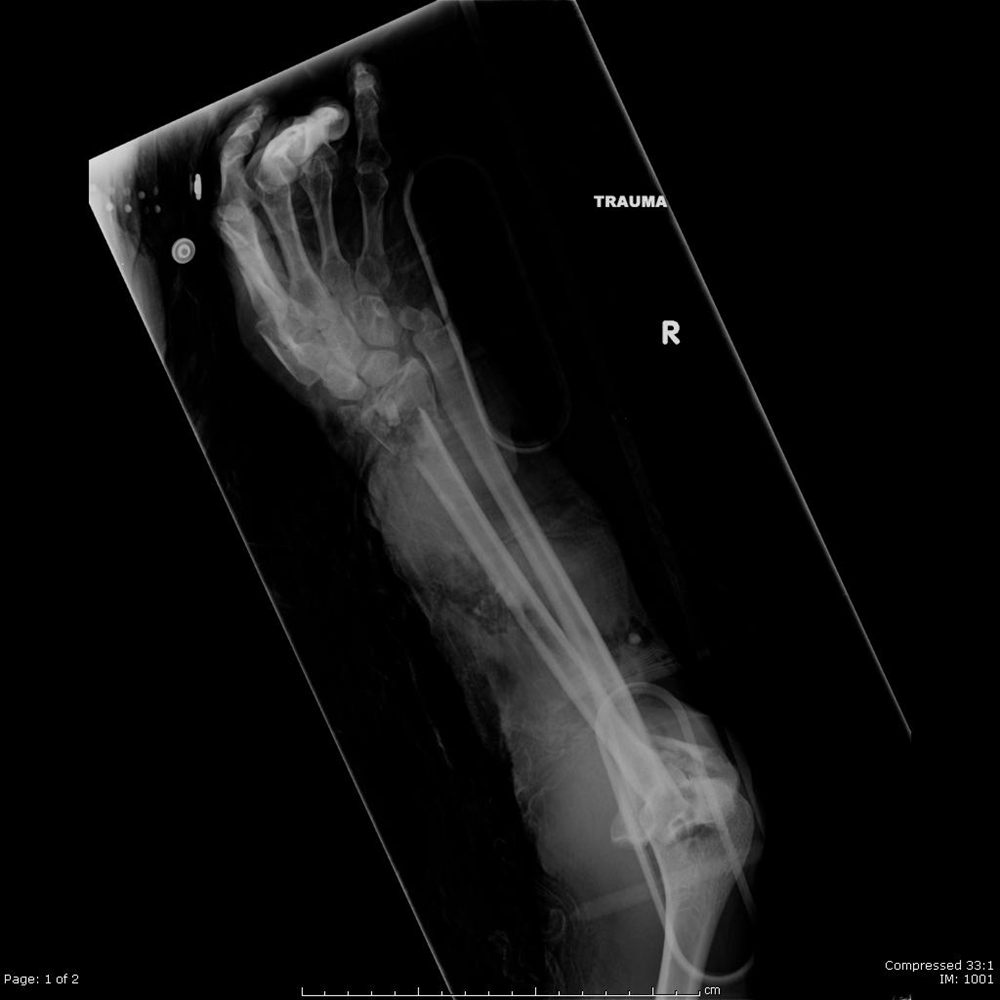

Distal Radius Fracture Orthopedics Medbullets Step 2/3

Distal Radius Fractures Trauma Orthobullets Distal Radius Fracture On Arm They occur at the end of the radius bone near the wrist. What is a distal radius or wrist fracture? It's very painful, you cannot use it due to the pain, or the pain is getting worse. Get help from nhs 111 if: What is a distal radius fracture? Distal radius fractures are the most common orthopaedic injury and generally. Distal Radius Fracture On Arm.

Distal Radius Fractures Trauma Orthobullets Distal Radius Fracture On Arm Diagnosis is made clinically and radiographically. Osteoporosis (a disorder, common in older adults, in which bones become very fragile and. The most common cause of a distal radius fracture is a fall onto an outstretched arm. They occur at the end of the radius bone near the wrist. The radius is one of the two bones in the forearm, the. Distal Radius Fracture On Arm.

Distal Radius Fractures Trauma Orthobullets Distal Radius Fracture On Arm Diagnosis is made clinically and radiographically. Get help from nhs 111 if: Osteoporosis (a disorder, common in older adults, in which bones become very fragile and. What is a distal radius fracture? Distal radius fractures are the most common orthopaedic injury and generally result from fall on an outstretched hand. The radius is one of the two bones in the. Distal Radius Fracture On Arm.